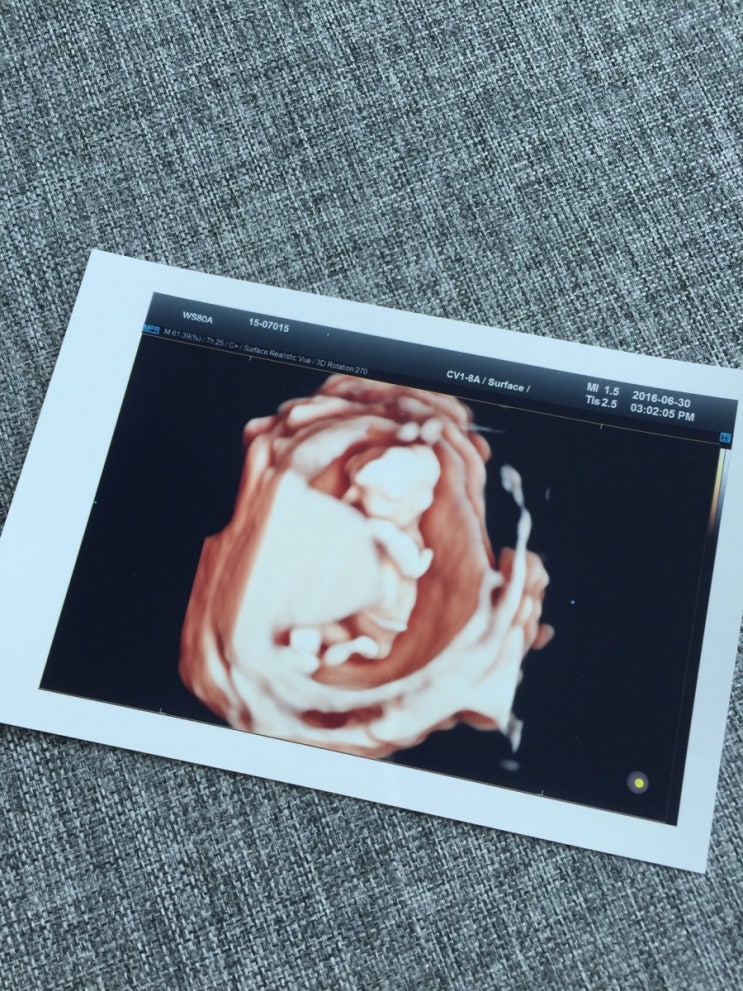

28주차 임산부 일상

별거 없는 28주차 임산부 일상. 컴퓨터로 블로그 하는 게 백만년 만인데 나 같은 기계치&컴맹은 너무 ...

그간 우리 부부에게는, 아기천사가 찾아왔다 한번의 유산이 있었으므로 물론 말할수 없이 기쁘기도 했지만 ...